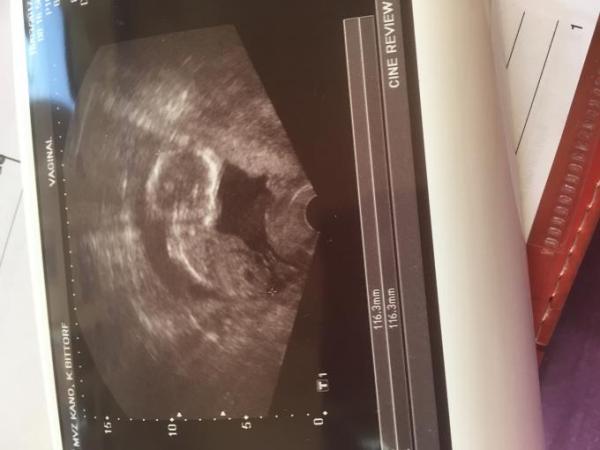

Hallo mal eine Frage. Kann man da was erkennen? Junge oder Mädchen??? FA wollte sich noch nicht äußern Danke für antworten Bin 16+4 ssw

Bild zu Frage zum Geschlechter - Schwanger - wer noch? Rund um die Schwangerschaft

Persönlich kann ich dort weder das eine noch das andere erkennen.... Ich sehe nur ein Baby ♡ Für das Geschlecht musst du schon ein Bild zw den Beinen haben. Wenn der FA sich schon nicht festlegt war es vielleicht einfach nicht sicher zu erkennen.